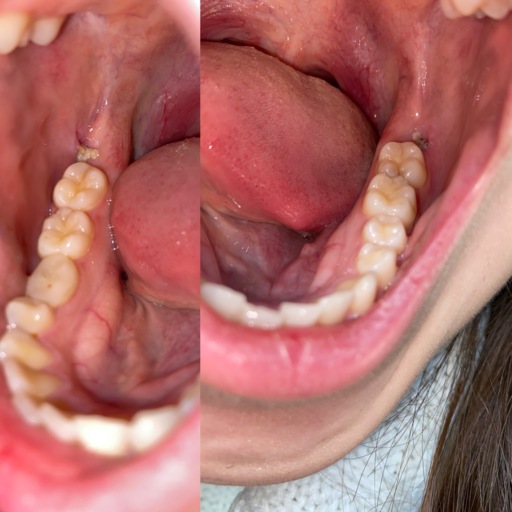

Impacted Canines

What is the procedure for impacted Canines that are at the top only for both canines and they are in the top of the gums on the outside (not in palette). I have an X-ray. ITS FOR MY DAUGHTER... 12 years old and 2 months.